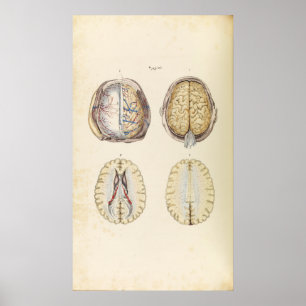

Póster Ilustração do cérebro humano do vintage

Preço25,25 €